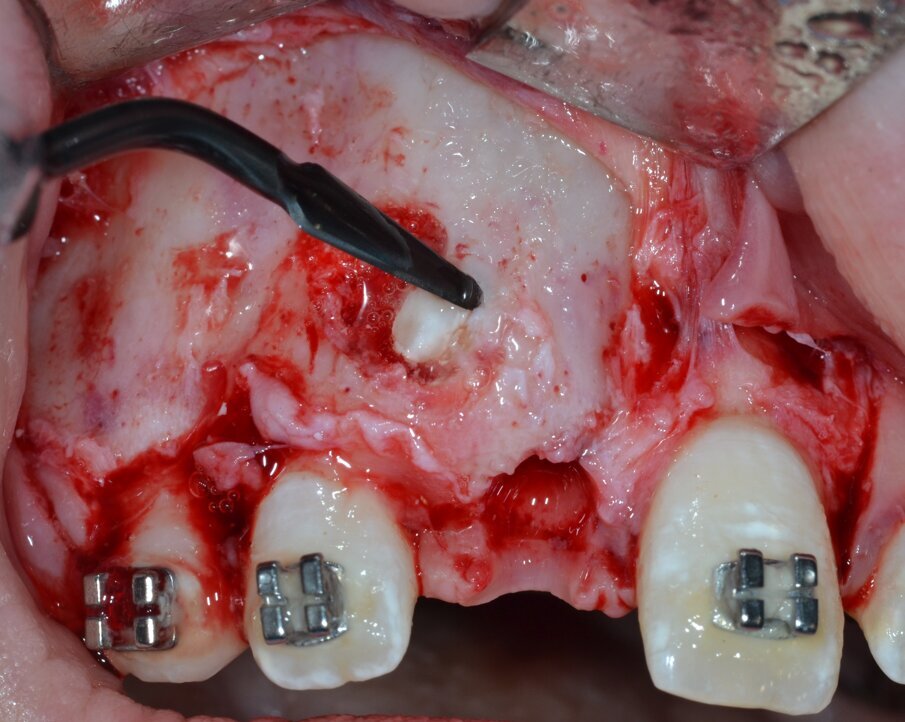

Si procede al clivaggio e all’enucleazione in toto della massa neoformata mediante una leva dritta (Fig. 9) seguita da un’accurata revisione chirurgica della cripta ossea residua (Fig. 10). Il pezzo operatorio viene inviato per l’esame istologico, che confermerà in via definitiva la diagnosi di odontoma composto (Figg. 11, 12). Poiché il piano di trattamento prevede di eseguire l’ancoraggio ortodontico dell’elemento ritenuto nella stessa seduta operatoria, la corona dentaria dell’elemento 1.1 viene esposta chirurgicamente per mezzo di un inserto piezoelettrico dedicato montato su un manipolo ad ultrasuoni (ES010T Esacrom Srl, Imola, Italia) (Fig. 13).

Fig. 10_Revisione chirurgica della cripta ossea residua.

Fig. 11_Misurazione ex vivo del pezzo operatorio.

Fig. 12_Confezionamento e invio del pezzo operatorio per esame istologico.